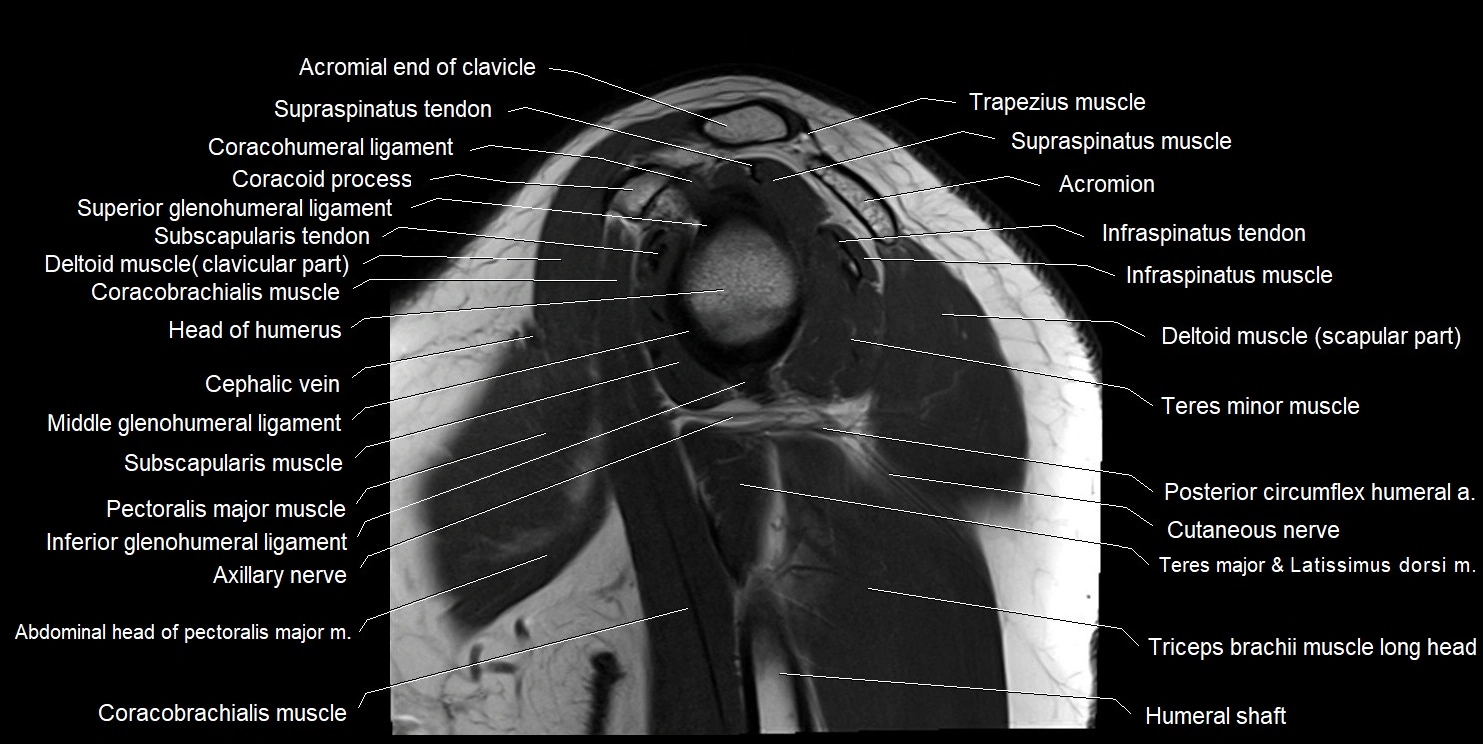

MRI images

image